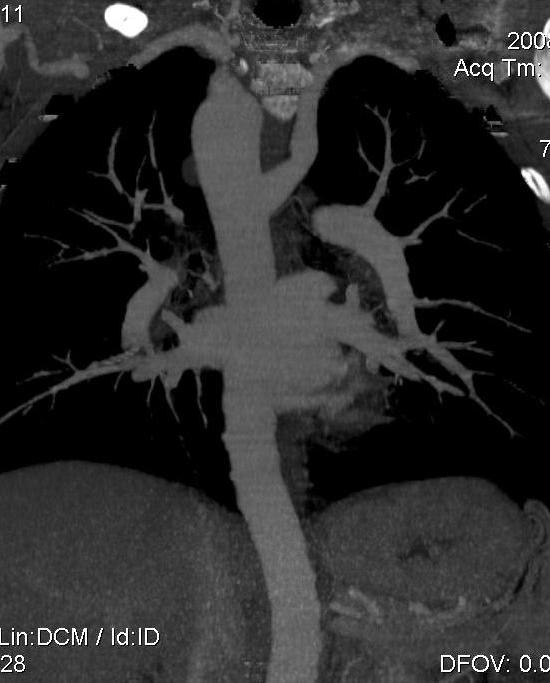

Пациент был направлен на КТ после рентгенографии ОГК, с направительным диагнозом: объёмное образование верхнего средостения.

это аномально расположенная грудная аорта

Конечно, дуга аорты идёт справа от позвоночника (декстра позиция); но есть и ещё одна аномалия той же группы: